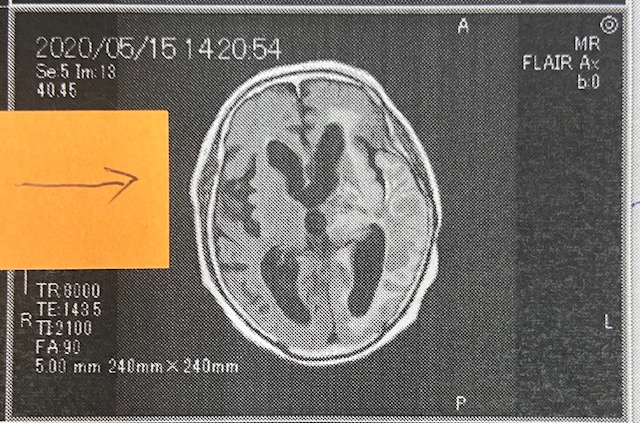

脳腫瘍の浮腫が2カ月で改善された画像です!!

先日、書いてます患者さんの画像をご覧ください。